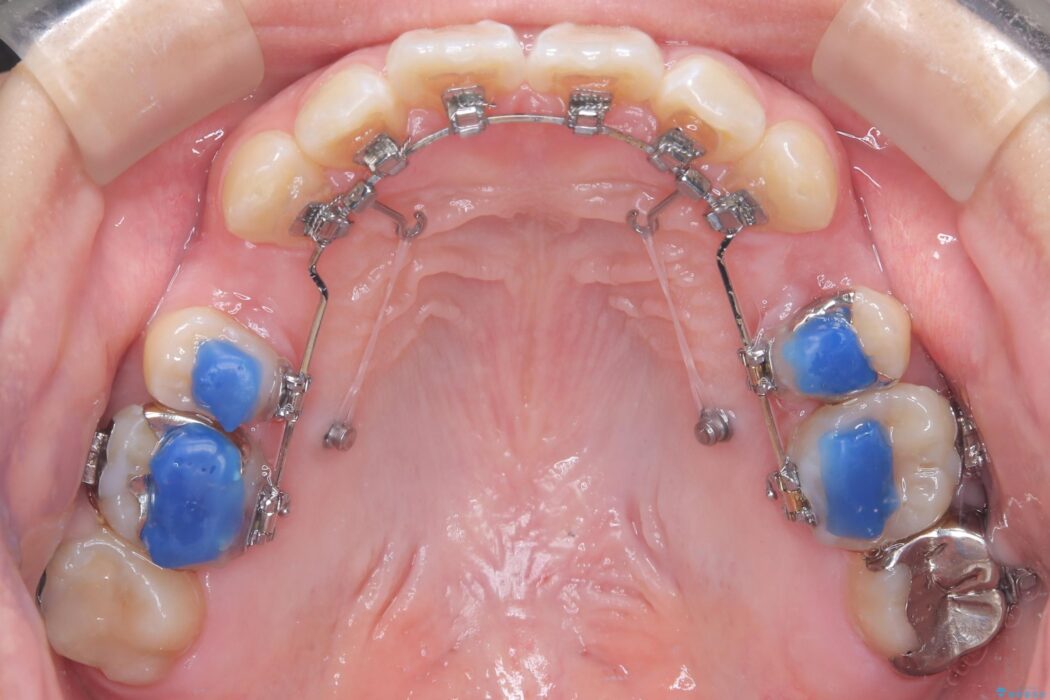

装置は人目を気にせず治療できるよう、上顎に裏側矯正、下顎に表側矯正を組み合わせたハーフリンガル矯正を提案しました。

装置には、上顎には目立たない裏側矯正(舌側矯正)を、下顎には透明な審美ブラケットを使用するハーフリンガル矯正を採用しました。抜歯によってできたスペースを最大限に活用し、前歯を効率よく後方へ移動。治療の結果、口元の突出感が大幅に解消され、Eライン(横顔の美しさの基準)も改善しました。人目を気にすることなく治療を完遂し、自信の持てる美しい横顔を獲得していただけました。